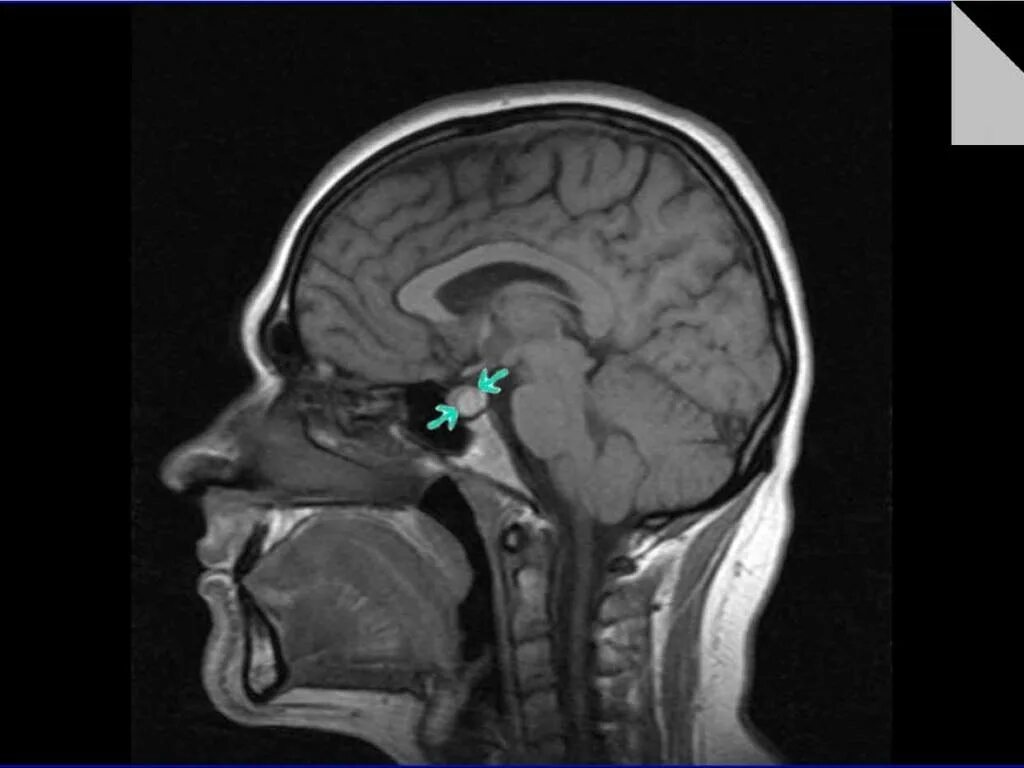

Опухоль гипофиза